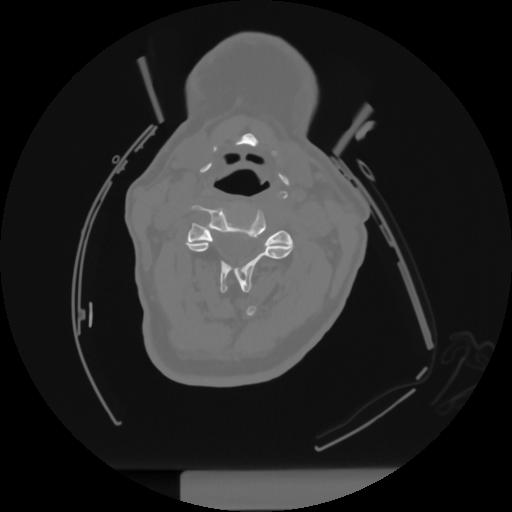

12 P.BLANDAS,,Vol,0.5,P.BLANDAS,,